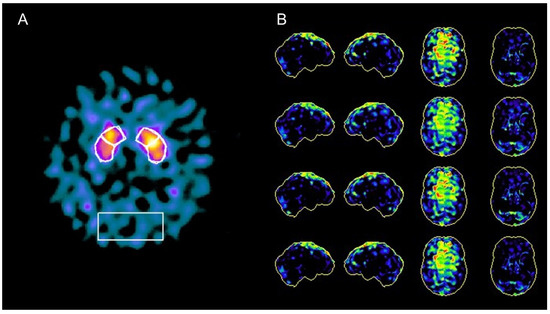

A 63-year-old man, with no previous history of neurological disorder, presented with a one-year history of slowness of movement as well as gait difficulties with postural instability and complained of episodes of falls and swallowing problems. He also reported a five-year history of vivid dreams with dream-enacting behaviour, suggestive of REM sleep behaviour disorder (RBD), and a two-year history of erectile dysfunction. Six months before the visit, he developed laryngeal stridor during sleep and severe nocturnal dyspnea attacks resulting in acute respiratory failure requiring intubation and subsequent tracheostomy. His family history was negative for neurodegenerative disorders. A neurologic examination showed horizontal gaze-evoked nystagmus, bradykinesia, rigidity, and mild rest and postural tremor that was more evident on the left side. He had reduced right arm swing when walking and a shuffling gait. Neuroimaging studies were carried out to differentiate atypical parkinsonian syndromes and to rule out alternative diagnoses. A structural brain 3T MRI showed temporal atrophy with relative preservation of other cortical areas and demonstrated high-convexity tight sulci (Figure 1). Subcortically, midbrain atrophy was evident (the “hummingbird” sign). An arterial spin labelling (ASL)-MRI documented relative hyperperfusion of the high-convexity area with relative preservation of other brain regions. Brain perfusion SPECT imaging confirmed relative hyperperfusion in the high-convexity area. [123I] FP-CIT SPECT demonstrated a bilateral dopaminergic nigrostriatal denervation more prominent in the right putamen. The magnetic resonance parkinsonism index (MRPI 2.0) [1], a reliable imaging morphometric marker for the diagnosis of progressive supranuclear palsy (PSP), was manually calculated and was suggestive of PSP. A routine CSF analysis was unremarkable, and CSF amyloid beta (Aβ42) and tau (total and phosphorylated tau) levels were normal. Although the clinical and radiological presentation was suggestive of PSP, some elements were atypical. First, vertical supranuclear palsy or slow velocity of the vertical saccades, which are clinical features with high diagnostic relevance for PSP, were absent in this patient. Second, laryngeal stridor is rare in PSP and is typically present in other atypical parkinsonisms, such as multiple system atrophy. Recently, a new disorder characterized by nonREM and REM parasomnias, stridor, and gait instability resembling PSP (PSP-like syndrome) has been described, which occurs in association with antibodies against extracellular epitopes of IgLON5, a neuronal cell adhesion protein. Autoantibodies for IgLON5 IgG were tested in both the serum and CSF using a commercially available cell-based assay and returned positive in our patient (Supplementary Figure S1).

Anti-IgLON5 disease is a very rare clinical entity characterized by distinctive sleep disorders associated with a broad variety of neurological symptoms, such as parkinsonism with gait instability, bulbar symptoms, and dysautonomia. This condition has been first described in 2014 [2], and since then, more than 60 cases of anti-IgLON5 disease have been reported in the literature [3]. Its pathophysiology still remains unknown, but it seems to be the result of a combination of both autoimmune and neurodegenerative processes. Characteristic neuropathologic findings include a lack of inflammatory infiltrates, neuronal loss, gliosis, and neuronal accumulation of hyperphosphorylated tau protein (both 3-repeat and 4-repeat isoforms) found predominantly in the hypothalamus and the tegmental brainstem nuclei [2]. MRI findings are normal or nonspecific in 81.8% of cases [3,4,5]. The most frequent abnormality is brainstem atrophy [6]. Ioflupane SPECT abnormalities, though scarcely described, have been reported in anti-IgLON5 disease, probably reflecting nigrostriatal dopaminergic degeneration in the context of the tauopathy component of the disease [7]. In this case, midbrain atrophy documented by a structural MRI and dopaminergic denervation shown by a dopaminergic SPECT oriented initially for a diagnosis of PSP. Furthermore, the imaging morphometric marker MRPI was also indicative of PSP. Interestingly, the MRI also demonstrated “high-convexity tight sulci”, an established neuroimaging biomarker of CSF dynamics disorders and defined as compression of sulci at the vertex, enlarged CSF spaces in the Sylvian fissure, and ventriculomegaly. Although “high-convexity tight sulci” was originally identified in individuals with symptomatic normal-pressure hydrocephalus (NPH), it has been also found in other conditions [8]. Similarly, hyperperfusion of the high-convexity area on perfusion imaging has been previously linked to NPH [9]. We believe that relative convexity hyperperfusion in our case is apparent and may reflect the increased gray matter density of the convexity, as it has been demonstrated in NPH [9]. Although CSF dynamics abnormalities have been observed in other conditions [8], to the best of our knowledge, this is the first time that neuroimaging reveals CSF dynamics problems in anti-IgLON5 disease. This case highlights the fact that anti-IgLON5 disease can exhibit the clinical and radiological changes seen in PSP patients and that neuroimaging markers of CSF dynamics problems (“high-convexity tight sulci” on an MRI and hyperperfusion of the high-convexity on both an ASL-MRI and a perfusion SPECT) may be found in IgLON5. Further case descriptions and case−control neuroimaging studies are warranted to characterize neuroimaging abnormalities in this condition. Neuroimaging studies are also required because CSF dynamics abnormalities are detectable in vivo only, and neuropathological studies cannot be used to investigate this phenomenon. Although clinical presentation may be very distinctive, imaging biomarkers may potentially assist the diagnosis of this rare condition. The early recognition of anti-IgLON5 diseases is essential as immunotherapy seems to be crucial for clinical outcomes.

Figure 1. MRI findings in a case of anti-IgLON5 disease: (A,B) axial T1-weighted and T2-weighted sequences demonstrate marked temporal atrophy with relative preservation of other cortical regions; (C) sagittal T1-weighted brain MRI sequences show midbrain atrophy (the “hummingbird sign”); (D,E) axial T1-weighted and F T2-weighted sequences showed “high-convexity tight sulci”; “high-convexity tight sulci” is defined as the compression of sulci at the vertex, enlarged CSF spaces in the Sylvian fissure, and ventriculomegaly; (F) arterial spin labelling (ASL)-MRI documented hyperperfusion in the high-convexity area with relative preservation of other brain regions.

Figure 2. Nuclear imaging findings in a case of anti-IgLON5 disease: (A) [123I] FP-CIT SPECT showed dopaminergic nigrostriatal denervation, more prominent in the right putamen; (B) brain perfusion SPECT imaging documented relative hyperperfusion in the high-convexity area with relative preservation of other brain regions.